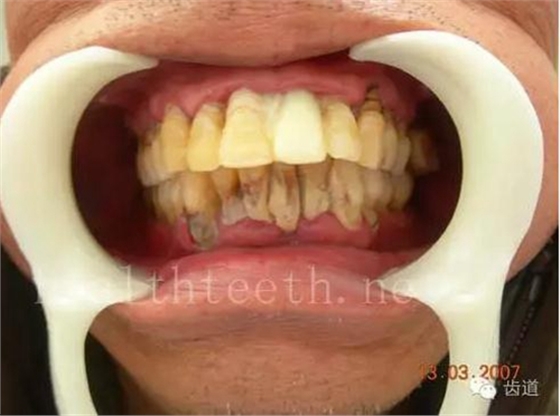

30歲人的口腔狀況